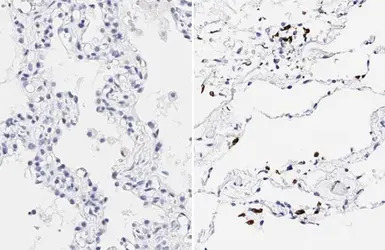

SARS-CoV-2 (COVID-19) Spike RBD antibody [HL257] detects SARS-CoV-2 (COVID-19) Spike RBD protein by immunohistochemical analysis.Sample: Paraffin-embedded non-infected (left) and infected (right) human placenta.SARS-CoV-2 (COVID-19) Spike RBD stained by SARS-CoV-2 (COVID-19) Spike RBD antibody [HL257] (GTX635692) diluted at 1:500.Antigen Retrieval: Citrate buffer, pH 6.0, 20 min

The IHC-P was performed by HISTOWIZ.

SARS-CoV-2 (COVID-19) Spike RBD antibody [HL257] detects SARS-CoV-2 (COVID-19) Spike RBD protein by immunohistochemical analysis.Sample: Paraffin-embedded non-infected (left) and infected (right) human lung.SARS-CoV-2 (COVID-19) Spike RBD stained by SARS-CoV-2 (COVID-19) Spike RBD antibody [HL257] (GTX635692) diluted at 1:1000.Antigen Retrieval: Citrate buffer, pH 6.0, 20 minThe IHC-P was performed by HISTOWIZ.